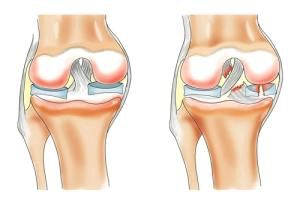

Розрив меніска і його основні типи

З'ясувавши вид, сторону і ступінь розриву, можна призначити лікування і точно сказати, чи можна взагалі зберегти хрящ.

Одним з найсерйозніших, на думку медиків, є повний односторонній розрив менісків.

Розглянемо можливі типи пошкоджень менісків: